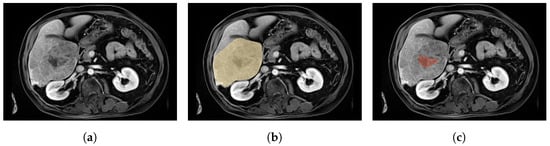

Figure 3.

Axial slices of CE-MRI showing different tumour shapes. (a) Axial slice of a CE-MRI from a patient with liver and simple tumour labels. (b) Axial slice of a CE-MRI from a patient with liver and multiple tumour labels. (c) Axial slice of a CE-MRI from a patient with liver and complex tumour labels.

HCC tumours can take various forms, as illustrated in Figure 3. The majority of the studied tumours take relatively convex forms, such as in Figure 3a. However, some cases may take heterogeneous forms with an atypical pattern (Figure 3c). Most of the time, these tumours are slightly harder to detect visually and therefore harder to delineate manually. In such cases, decreased accuracy for the label image may be assumed. Moreover, the infiltrating nature of HCC [25] may lead to multiple tumour components (Figure 3b). In addition, the tumour size varies widely across the dataset, with a maximum ratio of 850 between the largest and smallest tumours, corresponding to volumes of 2,188,369 mm and 2574 mm, respectively. The average tumour volume in the dataset is 341,442 ± 453,942 mm. In comparison, the ratio between the largest and smallest livers is only 5, with a liver size (healthy liver + unhealthy liver) that varies from 817,954 mm to 4,140,926 mm and an average volume of 1,988,183 ± 655,839 mm. Thus, the tumour burden () varies from to .